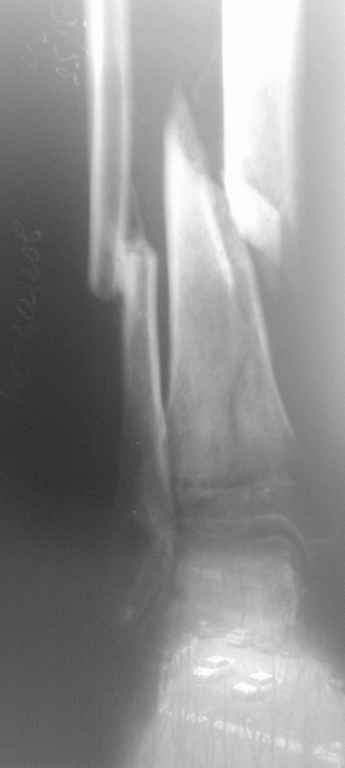

Д\з Неправильно консолидированный перелом м\берцовой кости, ложный сустав(учитывая подвижность в области перелома) б\берцовой кости правой голени. Остеопороз костей правой голени, стопы. Постиммобиллизационные контрактуры коленного, голеностопного суставов.

Больной Б. травма в августе месяце 2010г., находился на СВ, отказался от оперативного лечения, со слов больного, не имел средств на приобретение металлоконструкций, СВ вытяжение демонтировано ч\з 3 недели, была наложена циркулярная гипсовая повязка от кончиков пальцев стопы до с\3 бедра, снят 10 ноября, имеется Rg контроль по снятию повязки, первичных и после демонтажа СВ снимков не предоставил, почему не продолжил лечение на СВ, нет сведений.

Сейчас кожные покровы правой голени отёчны, пастозны, умеренно гиперемированны, движения в коленном суставе сгибание 90гр., разгибание 165, голеностопном в пределах качательных. Определяется подвижность в месте перелома. Осевая нагрузка болезненна. На консилиуме решено (учитывая отсутствие возможности наложения аппарата Илизарова) выполнить остеотомию м\берцовой кости остеопериостальную декортикацию б\берцовой кости,репозиция(возможно с укорочением) фиксацию отломков кортикальными винтами, циркляжом с последующим наложением циркулярной гипсовой повязки. Почему не было выполнено при первом поступлении или не доведена репозиция на СВ для меня вопрос.Заранее благодарен.